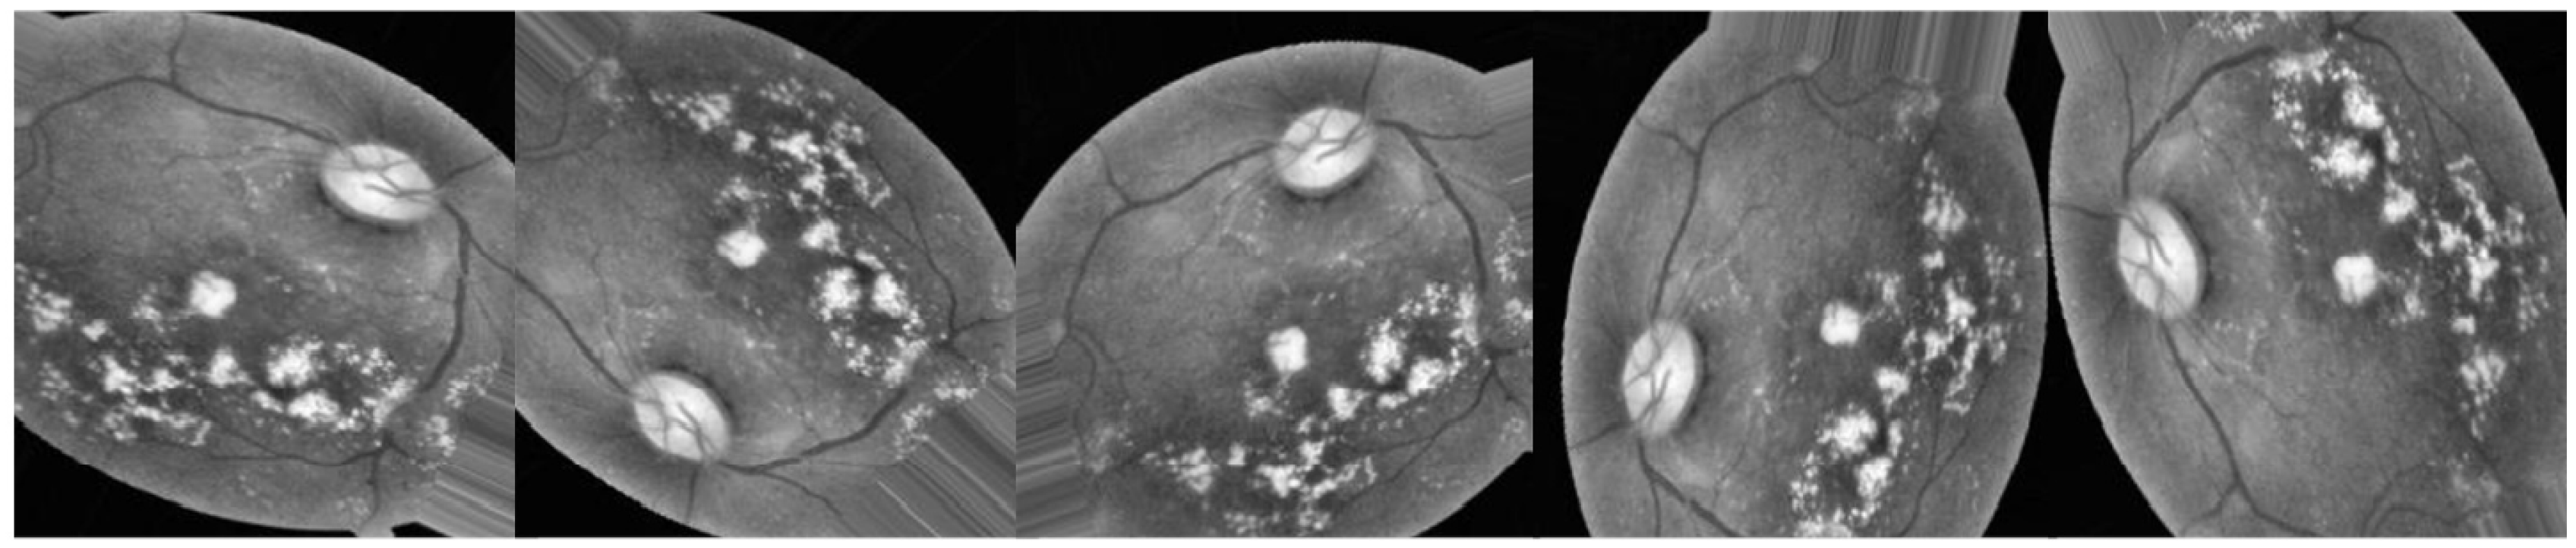

Lesions caused by MIA and HEM tend to be red, while blemishes caused by the two forms of exudates tend to be bright. There are five distinct stages of DR that can be detected: Different degrees of DR are shown in Figure 1: none, mild, moderate, severe, and proliferative DR [11].

Selecting a dataset with a sufficient number of high-quality photos is crucial. This study makes use of the APTOS 2019 (Asia Pacific Tele-Ophthalmology Society) Blindness Detection Dataset [14], a publically available Kaggle datasets that incorporates a huge number of photos. In this collection, high-resolution Retinal pictures are provided for the 5 stages of DR, classified from 0 (none) to 4 (proliferate DR), with labels 1-4 corresponding to the four levels of severity. There are 3,662 retinal pictures in total; 1,805 are from the "no DR" group, 370 are from the "mild DR" group, 999 are from the "moderate DR" group, 193 are from the "severe DR" group, and 295 are from the "proliferate DR" group as illustrated in Table 2. Images are 3216 x 2136 pixels in size, and Figure 1 shows some examples of these kind of pictures. There is background noise in the photographs and the labels, much like any real-world data set. It’s possible that the provided images will be flawed in some way, be it with artifacts, blurriness, improper exposure, or some other issue. The photos were collected over a long period of time from a number of different clinics using different cameras, all of which contribute to the overall high degree of diversity.

Figure 1. The five phases of diabetic retinopathy, listed by severity.